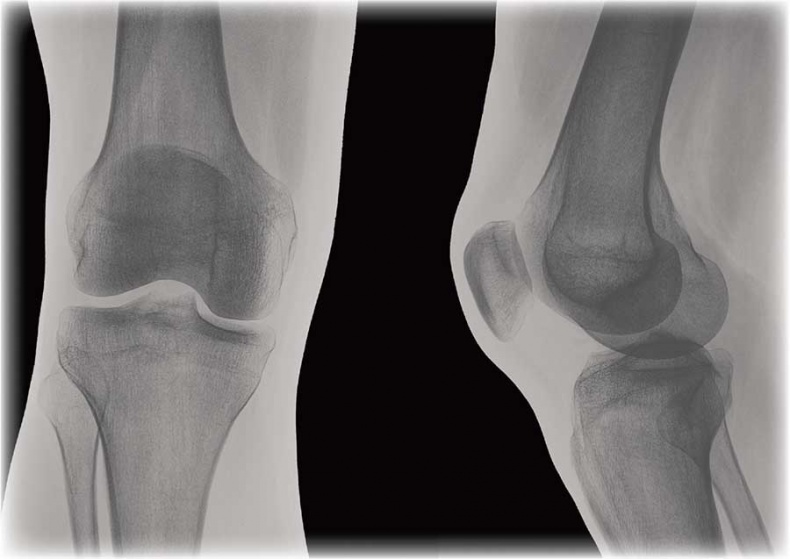

![]() Отделы позвоночника Движение позвоночника – результат работы многочисленных комбинированных суставов между позвонками. Он движется за счет действия скелетных мышц. Позвоночник способен наклоняться вперед, прогибаться (сгибание и разгибание), наклоняться вбок (отведение и приведение), а также скручиваться. Наиболее подвижны шейный и поясничный отделы. Химический состав костей взрослого человека следующий: 50 % воды, 15 % жира, 12 % органических веществ (белок, представляющий собой разновидность коллагена), 22 % неорганических веществ, а именно солей кальция в форме гидроксиапатита, и около 30 % органических веществ. Основные органические вещества кости – белки коллаген и оссеин. Сочетание волокон органического коллагена с солями кальция обеспечивает основные функции костей – прочность и упругость. Прочность – это способность противостоять внешним механическим воздействиям, упругость – возвращать первоначальную форму после окончания действия внешней силы. Минеральные вещества придают костям твердость и хрупкость, органические – гибкость и упругость. Благодаря сочетанию органических и неорганических веществ кости имеют большую прочность, что позволяет им выносить немалые нагрузки. ![]() Структура кости Соотношение органических и неорганических веществ с возрастом изменяется. В костях детей немного больше органических веществ, поэтому их кости более упругие, гибкие и реже ломаются. С возрастом в костях увеличивается доля неорганических веществ, из-за чего у пожилых людей кости менее эластичные и более хрупкие и могут ломаться даже при небольших травмах. Соединения костей связывают кости скелета в одно целое, обеспечивая им ту или иную степень подвижности. Различают три вида соединений: • непрерывные соединения, в которых полость между соединяющимися костями отсутствует, существует лишь прослойка соединительной ткани или хряща – неподвижные соединения; • переходная форма от непрерывных соединений к прерывным – симфизы, или полусуставы; имеют небольшую щель в хрящевой или соединительнотканной прослойке между сочленяющимися костями – эти образования обладают большой прочностью и очень ограниченной подвижностью; • прерывные (синовиальные) соединения или суставы; характеризуются наличием между костями полости и синовиальной оболочки, выстилающей изнутри суставную капсулу, – это подвижные соединения, а степень подвижности зависит от особенностей строения конкретного сустава. Сустав – самая распространенная и сложная форма соединения костей. Обязательными элементами любого сустава, независимо от места расположения и степени подвижности, являются суставные поверхности, суставная сумка и суставная полость. ![]() Соединение костей в коленном суставе (вверху – рентген, внизу – модель) ![]() Суставные поверхности костей, образующие сустав, плотно прилегают друг к другу. Они покрыты особым гиалиновым хрящом, чья гладкая поверхность и эластичность облегчают движение в суставе, смягчают испытываемые им толчки и сотрясения. Суставные поверхности костей окружает суставная капсула – оболочка из соединительной ткани. Обычно она крепится к костям в месте перехода суставной поверхности в надкостницу и прочно с ней срастается. Снаружи капсула укреплена связками, которые располагаются в местах наибольшей нагрузки. Суставные поверхности и капсула ограничивают собой небольшое герметично закрытое пространство – полость сустава, заполненную малым количеством вязкой синовиальной жидкости, роль которой заключается в уменьшении трения в суставах при движении. Благодаря отрицательному давлению в суставной полости поверхности костей тесно прилегают друг к другу. ![]() Суставная капсула ![]() Шаровидный сустав По форме суставных поверхностей различают плоские, цилиндрические, эллиптические и шаровидные суставы. Наименее подвижны плоские суставы, наиболее – шаровидные. Так как мы существуем в трехмерном пространстве, то в биомеханике суставов соответственно выделяют три оси вращения: фронтальную (правая – левая стороны, или наружная – внутренняя поверхности), сагиттальную (задняя – передняя поверхности) и продольную (вдоль сочленяющихся костей). В зависимости от формы суставных поверхностей в суставах может быть движение вокруг любой одной, двух или трех указанных осей (одно-, двух- и многоосные суставы). Вокруг указанных осей выполняются соответствующие виды движений. Вокруг фронтальной оси происходят сгибание и разгибание. При сгибании угол между сочленяющимися костями уменьшается (например, в локтевом суставе – угол между плечом и предплечьем). Во время разгибания движение идет в обратном направлении и происходит выпрямление (конечности или туловища). Вокруг сагиттальной оси осуществляются приведение и отведение. В случае отведения одна из сочленяющихся костей удаляется от срединной плоскости, при приведении – приближается к ней (например, отведение руки в сторону от туловища и снова приближение к нему). ![]() Наши двигательные возможности определяются прежде всего строением суставов Вокруг продольной оси кость вращается в разные стороны. Круговое движение – это последовательное перемещение вокруг всех осей, при котором свободный конец движущейся кости или конечности (например, кисти руки) описывает окружность. Размах (объем) движений в суставах зависит от многих факторов: • от разности угловых величин (выражаются в угловых градусах) сочленяющихся поверхностей (чем больше эта разность, тем больше размах движений); |